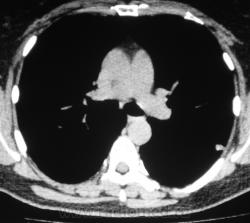

Произведена КТ.

КТ хотелось бы посмотреть в dicom-формате, меняя режимы, но на мой взгляд образование содержит известковые включения. Хотя, я не настаиваю, дождемся мнения коллег.

Нет "волшебных методов", можна поставить диф. ряд. Я бы дала такое заключение: хондрогамартрома, дифференцировать с туберкуломой, периферический рак менее вероятен. Можно жизнь прожить с гамартромой, а может озлиться в саркому. На практике был случай, когда лет 10 наблюдалась классическая скиалогически туберкулома, которая за полгода выросла и оказалась аденокарциномой. Таким образом, при любом раскладе, хирургическое лечение не является ошибкой, но решение об операции на легком должен принимать консилиум.

Дело не в желании, а в смысле. Что тут ещё можно сказать? На мой взгляд-мелкая, частично кальцинированная туберкулома.

Да, более туберкулёма.